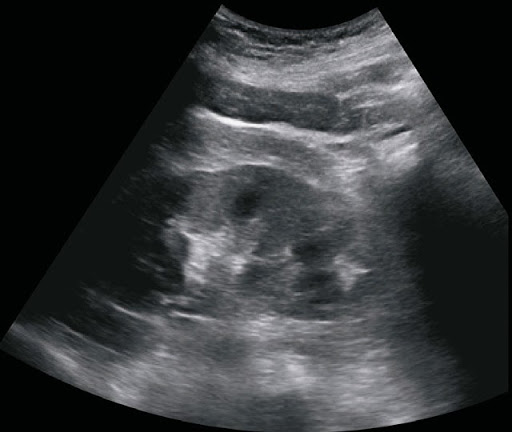

B-режим

- Абдоминальные исследования

Абдоминальные |

Мочевой пузырь, протоки, печень, поджелудочная железа, почки, селезенка, опухолевые образования (SOL), аорта, портальная вена, стеноз, почечный кровоток и др |